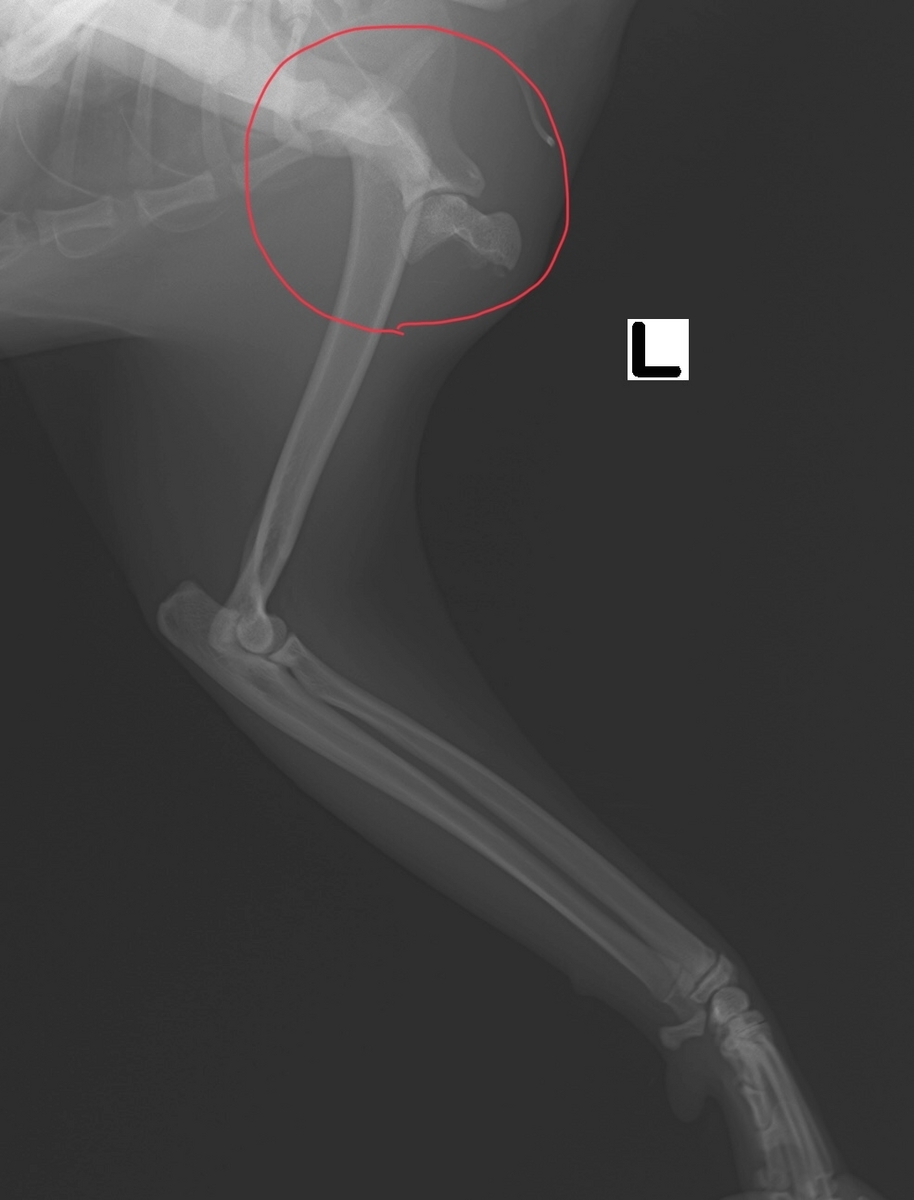

レントゲン検査にて、左上腕骨近位の成長板骨折が確認できました。